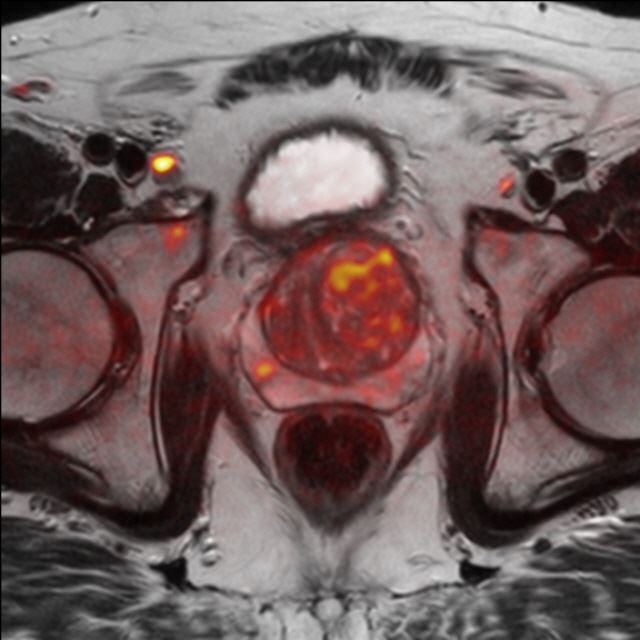

Prostata (mpMRT)

Die multiparametrische MRT der Prostata (mpMRT) bietet eine gute Möglichkeit, mittels bildgebender Diagnostik die Lokalisation, die Ausdehnung und eventuelle Aussaat eines Prostata-Karzinoms darzustellen. Die Untersuchung dient meist der Abklärung unklarer Tastbefunde, Ultraschallbefunde oder wiederholt erhöhter oder steigender PSA-Werte in der Labordiagnostik.

Die bildgebende Diagnostik der ersten Wahl ist zwar der Ultraschall mit einer Spezialsonde beim Urologen und ggf. die ultraschallgesteuerte Stanzbiopsie verdächtiger Befunde. Bei fehlender Darstellung des Tumors im Ultraschall oder vergeblichen Biopsien kann aber die MRT als Problemlöser eingesetzt werden: Sie zeigt dem Urologen, wo eine weitere Biopsie die Diagnose sichern kann. Außerdem kann die MRT bei ausgedehnten Tumoren einen Überblick über die Beteiligung der Nachbarorgane verschaffen und Absiedlungen (Metastasen) entdecken.